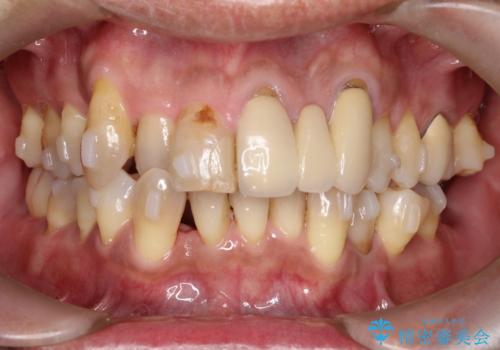

- 50代の患者様で、右上の八重歯と歯並びの乱れを気にされてご来院されました。特に、すでに装着されている前歯のセラミックブリッジを外したくないという強いご希望がありました。精密な検査の結果、八重歯を治すためのスペースが不足しているため、右上の4番目の歯(小臼歯)を抜歯し、そのスペースを利用して歯並び全体を整える治療計画を立案。装置には目立たないインビザラインを採用し、ブリッジを温存しながら八重歯の改善を目指しました。

今回の治療で最も重要だったのは、患者様のご要望通り既存のセラミックブリッジを外さずに矯正を進める点でした。計画通り右上の小臼歯を抜歯し、透明なインビザラインを使用して抜歯スペースを閉じながら、八重歯を正しい位置へ移動させました。ブリッジの形態と調和するに、他の歯の移動を工夫をすることで、複雑な条件をクリア。治療の結果、長年気にされていた八重歯が解消され、見た目が大きく改善しました。50代からでも、ご自身の要望を叶えながら、美しく機能的な歯並びを獲得していただけました。